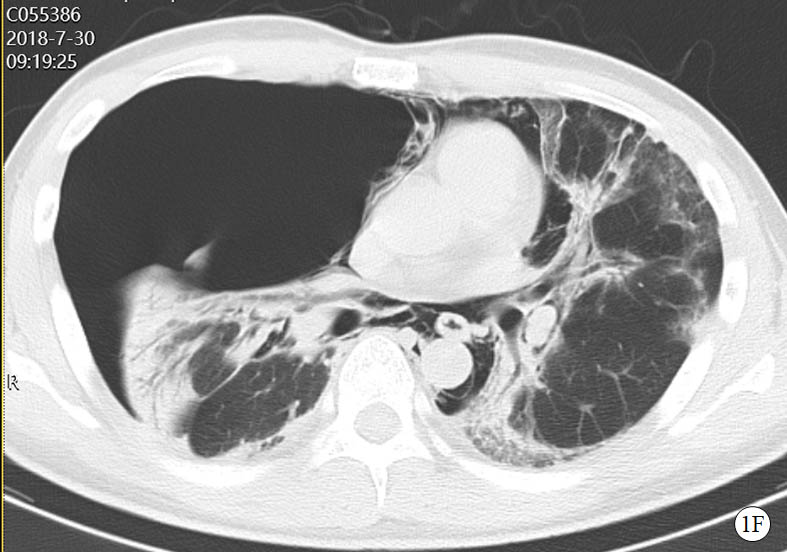

图 1 患者口服百草枯后胸部CT影像学变化

2018-07-30 CT图